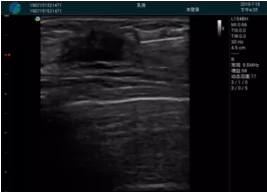

清晰顯示孕囊,通過軟件包計(jì)算孕齡7w+6d

M20實(shí)時(shí)引導(dǎo),術(shù)中清晰顯示孕囊被破壞和抽吸針的過程,清晰顯示吸引針

抽吸結(jié)束后縱切子宮,孕囊已被完全抽吸,未見明顯殘留

橫切子宮,發(fā)現(xiàn)右側(cè)宮腔靠近宮角處有少許脫模樣殘留

M20引導(dǎo)下,抽吸針找到右側(cè)宮角處再次清掃

二次抽吸后再次進(jìn)行超聲檢查,宮腔未見殘留,宮腔線清晰顯示